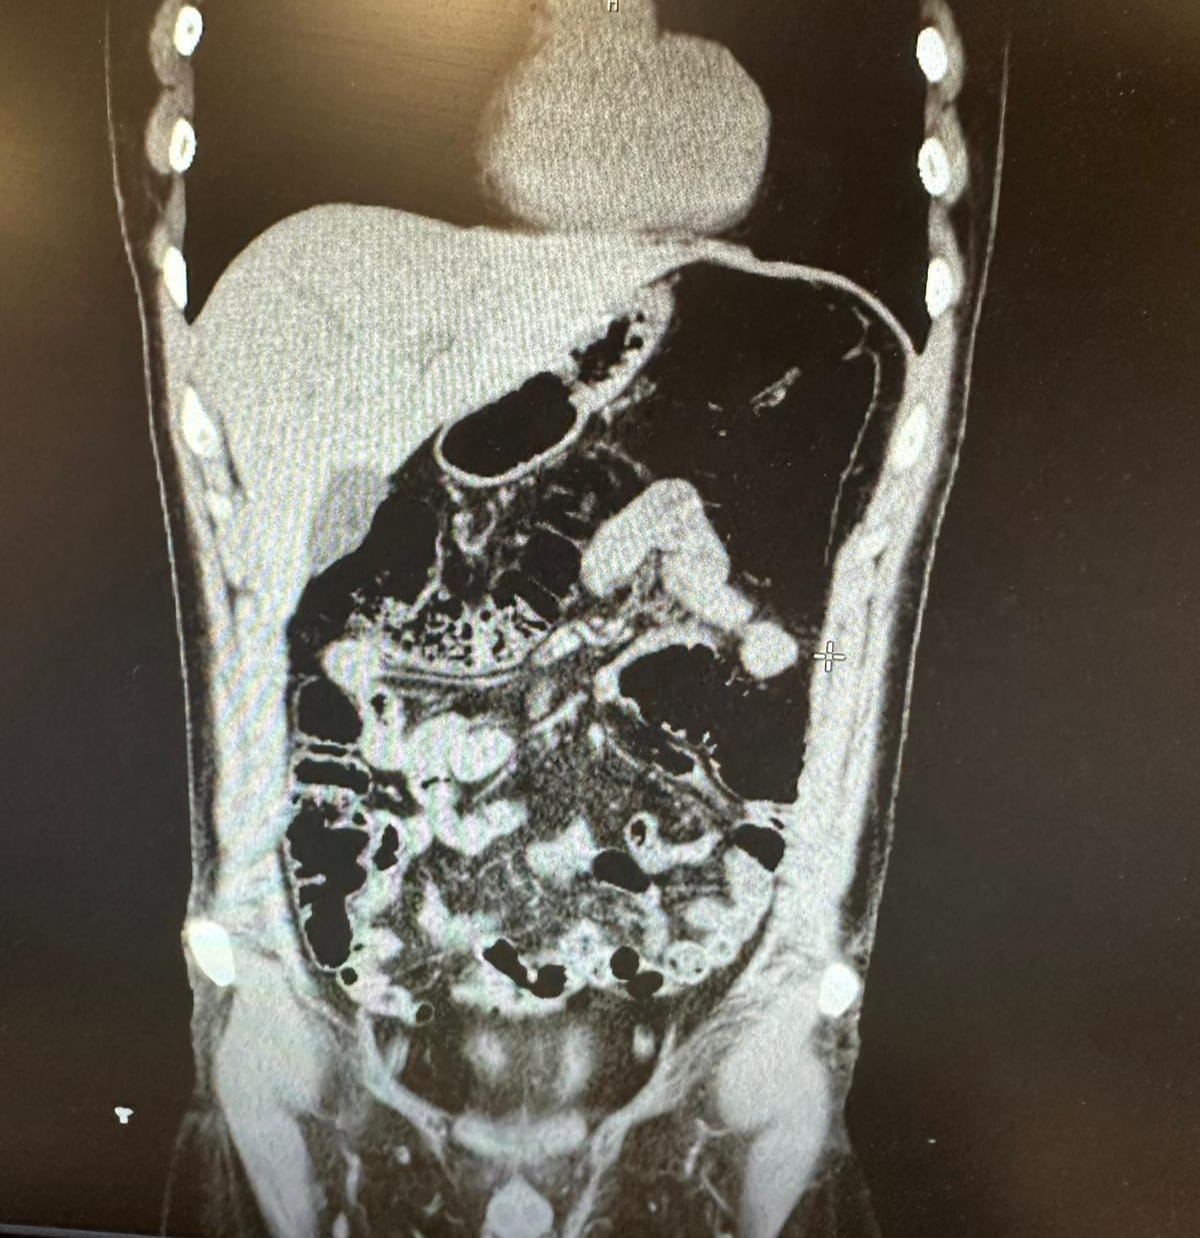

Ekiplerin titizlikle yürüttüğü saha çalışmalarında uyuşturucu kuryeliği yapan İran uyruklu bir şahıs tespit edildi. Polis, şüphelinin Konya’da gizlendiği adresi tespit ederek operasyon düzenledi. Şüpheli ve beraberindeki 4 kişi gözaltına alındı. Şüphelinin uyuşturucu yuttuğunu ifade etmesi üzerine hastaneye kaldırıldı. Şüpheli, 2 gün boyunca polis nezaretinde hastanede gözlem altında tutularak midesinde kapsüller halinde bulunan eroin maddesi doğal yollarla dışarı çıkarıldı.

Konya’da konakladıkları evin tespit edilmesiyle 1’i İran uyruklu 5 şüpheli yakayı ele verdi. İran uyruklu Vahıd Farhang Gangachı’nin midesinde 300 gram, gizlendiği adreste ise Narkotik köpeği Alex ile yapılan aramada ise toplam 6 parça halinde 1 kilogram eroin, bir miktar metamfetamin ve bir miktar uyuşturucu hap ele geçirildi.